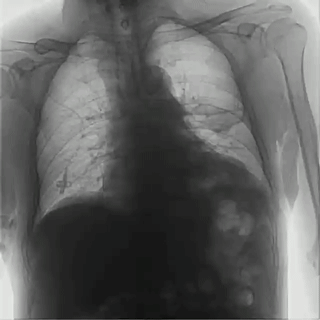

胸透影像

動態(tài)平板DRF通過可視化功能進(jìn)行動態(tài)觀察,影像清晰流暢,能夠捕捉到呼吸過程中肺部的細(xì)微變化,有助于醫(yī)生觀察肺部的運(yùn)動和擴(kuò)張情況,尤其是在診斷哮喘、慢性阻塞性肺病(COPD)等疾病時,對肺功能的評估更加準(zhǔn)確。同時,通過多角度的動態(tài)觀察,可以幫助醫(yī)生更加全面地評估呼吸系統(tǒng)疾病,對于一些在靜態(tài)影像中不易察覺的病灶,動態(tài)平板DRF能夠通過連續(xù)的影像捕捉到細(xì)微變化,從而降低漏診和誤診的風(fēng)險。動態(tài)平板DRF成像速度快,醫(yī)生能夠即時觀察并分析呼吸系統(tǒng)的動態(tài)變化,提高診斷速度,對于需要快速診斷的急性呼吸系統(tǒng)疾病諸如氣胸、肺栓塞尤為有利。